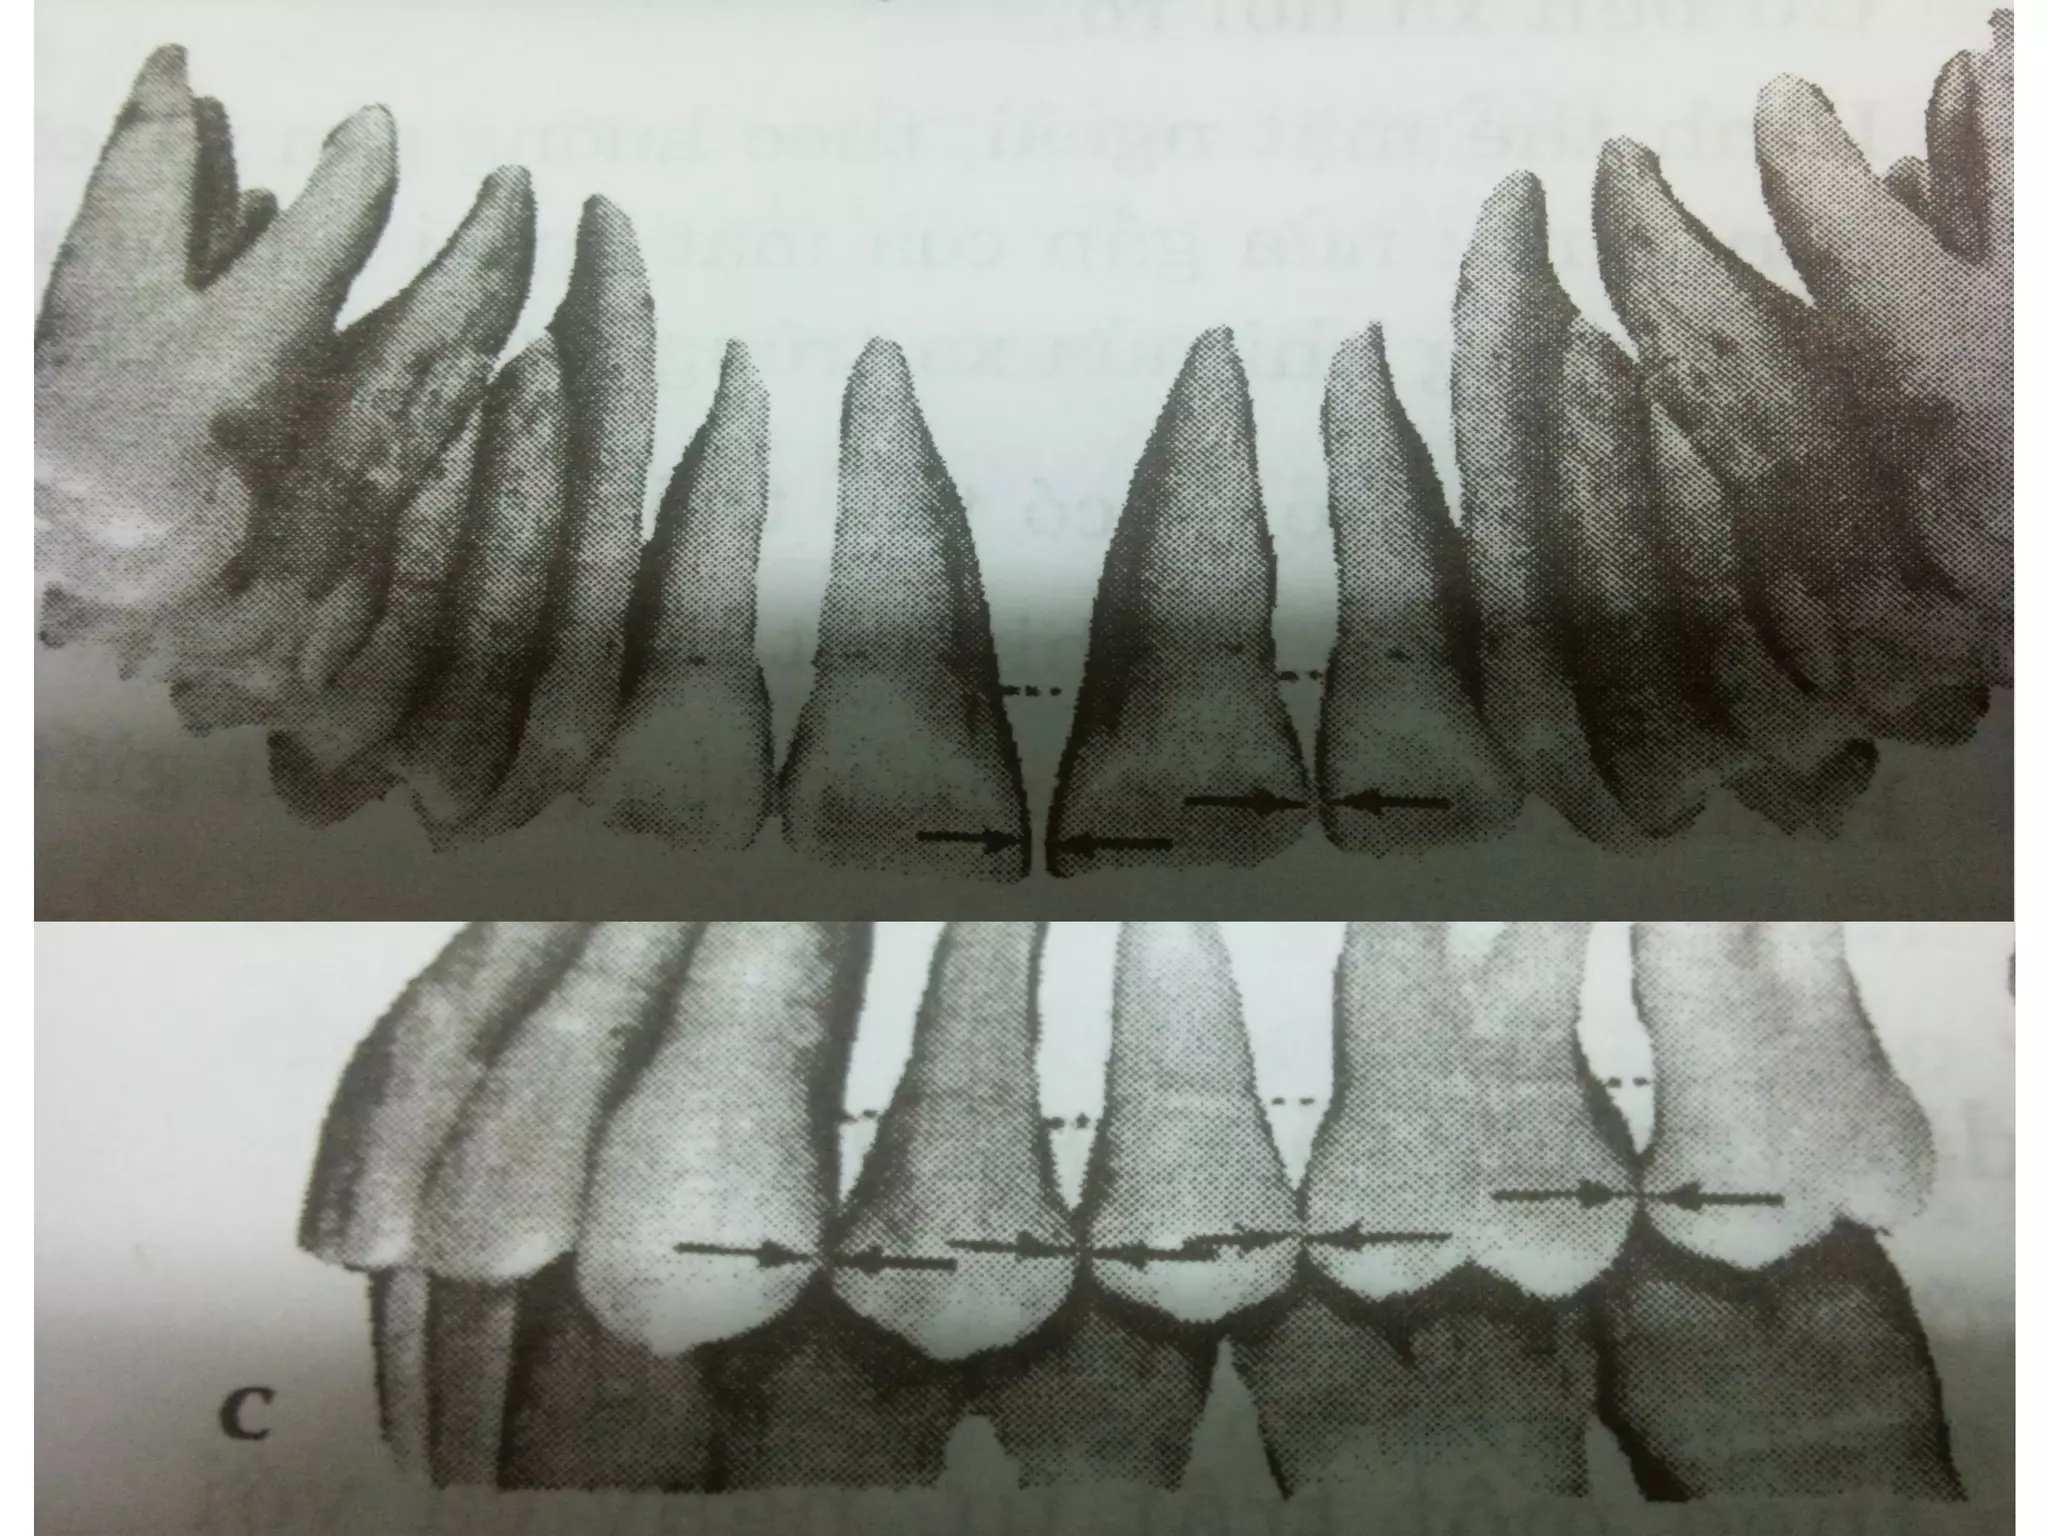

Tương quan theo chiều ngoài trong

Tương quan theo chiều gần xa

Tương quan theo chiều đứng

Đặc điểm sự ăn khớp giữa các răng của hai hàm

- Một răng tiếp xúc với hai răng ở hàm đối diện

- Ở hàm dưới, một răng nằm ở phía gần hơn và

trong hơn so với răng cùng tên ở hàm trên

- Mỗi răng dưới trong tư thế lồng múi tiếp xúc

với hai răng trên